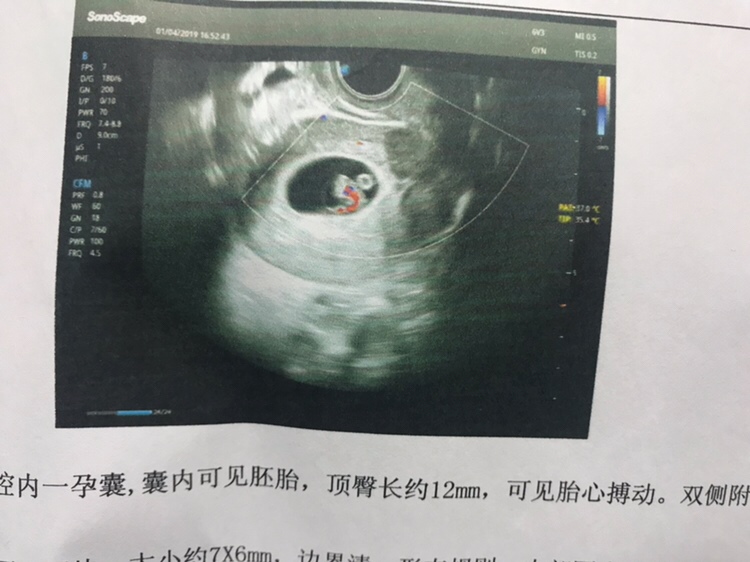

孕7周+0天